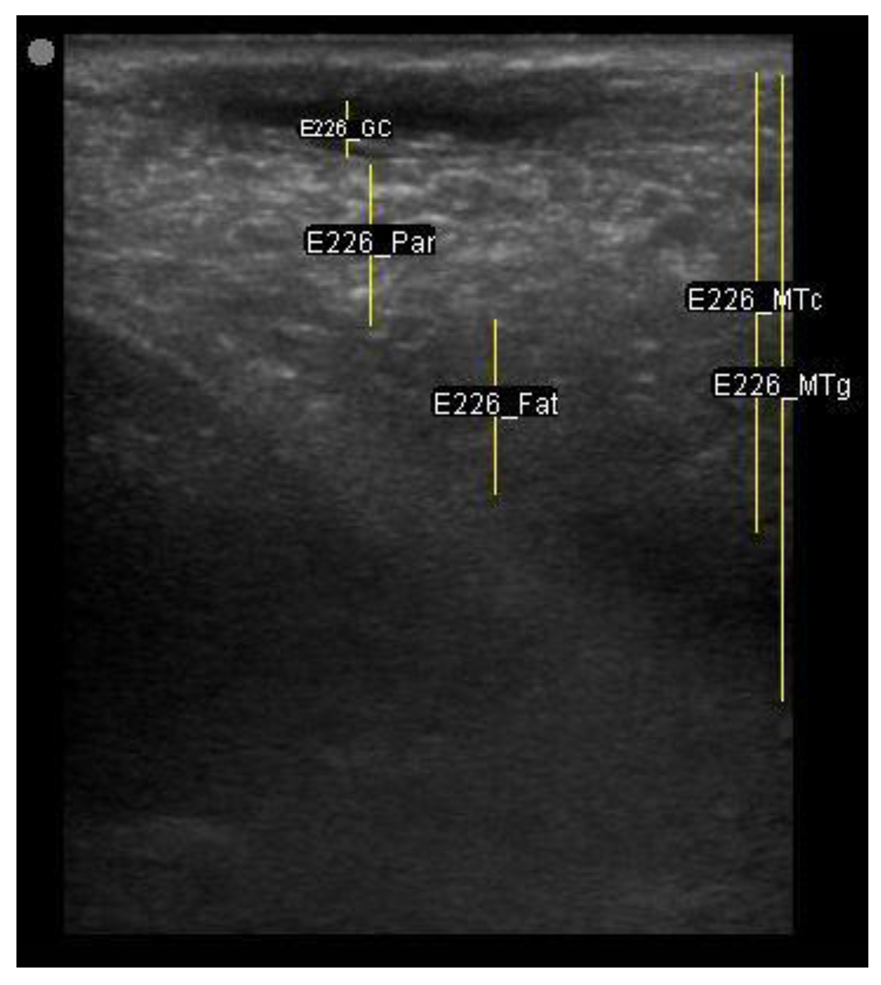

The image processing was undertaken using ImageJ software [28] as used by Abràmoff et al. [29]. The scales between pixels and millimetres were calculated based on the number of pixels, the scanning depth (mm), and the transducer width (mm) (Figure 4). This method relies on the ability of the operator to interpret and identify lines on the images. To standardize the assessment compartment depth, drawing templates were created for each time point as used by Molenaar et al. [30] and included four representative images from four different yearling ewes with and without the lines drawn for each compartment (Appendix A). The total depth of mammary gland conservative (MTc) was the smallest likely demarcation (abdominal wall) of the mammary gland (Figure 5a), and total depth of the mammary gland generous (MTg) was the largest likely demarcation of the mammary gland visible on the image [30] (Figure 5a). The MTc, MTg, fat pad (FP), parenchyma (PAR), and gland cistern (GC) depths were estimated at the deepest point for each sub-compartment, excluding the skin layers, using the straight tracer (Figure 5a) and were expressed in millimetres.

Figure 5.

(a) Demonstration of delimitations of the mammary total depth conservative (MTc) and generous (MTg), mammary gland cistern (GC), parenchyma (PAR) and the fat pad (FP) and (b) Demonstration of randomly positioning of regions of interest (1, 2, 3) in the parenchyma.

Drawing template of mammary ultrasound images in early lactation (29 days of lactation; L29) in four different yearling ewes.